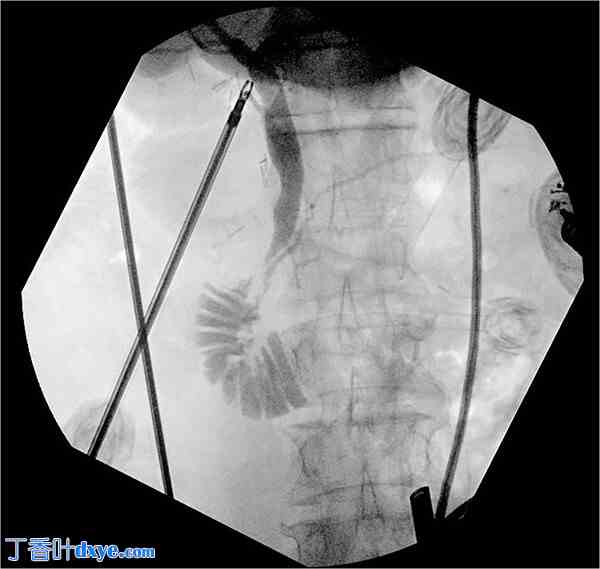

术中,鉴于覆盖十二指肠第二段的环状胰腺外观及解剖结构清晰,且患者既往开腹手术造成广泛粘连,决定行环状胰腺一期分离术以缓解十二指肠梗阻。在覆盖十二指肠第二段前部的环状胰腺后表面之间形成一个平面(图2,补充视频2),以便在此空间放置腹腔镜吻合器(Covidien 铰接式 Endo GIA™ 血管/中型三钉合器 45 毫米(金色)),从而横切环状胰腺(图3和图4,补充视频2)。由于患者胆结石广泛,因此还进行了腹腔镜胆囊切除术。术中胆管造影显示胰胆管连接畸形,胆管在壶腹部近端进入主胰管(图5,补充视频2),这是一种已知与环状胰腺相关的异常。将一根10-French Jackson-Pratt引流管置于腹部右上腹环状胰腺分割处上方。经腹腔镜放置腹膜内补片以修复患者多发性切口疝,并用经筋膜缝合线和AbsorbaTack™固定。

图 5.

术中胆管造影显示胰胆管连接不良,胆管在壶腹部近端进入主胰管。